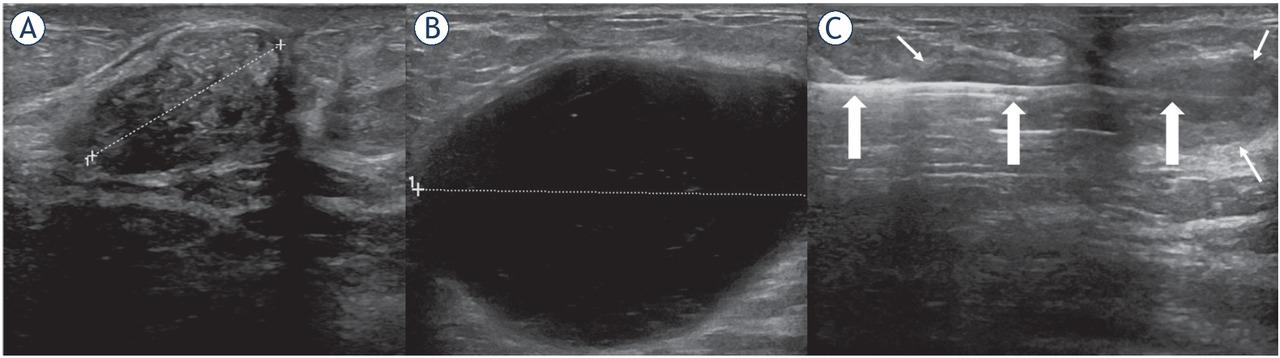

Figure 1